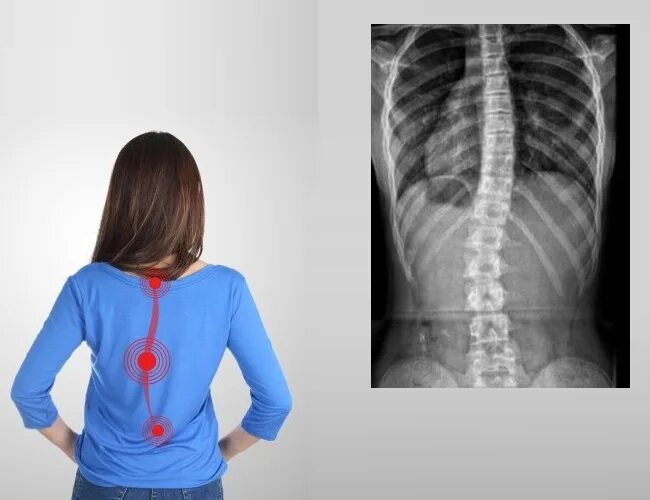

Сколиоз 2ст